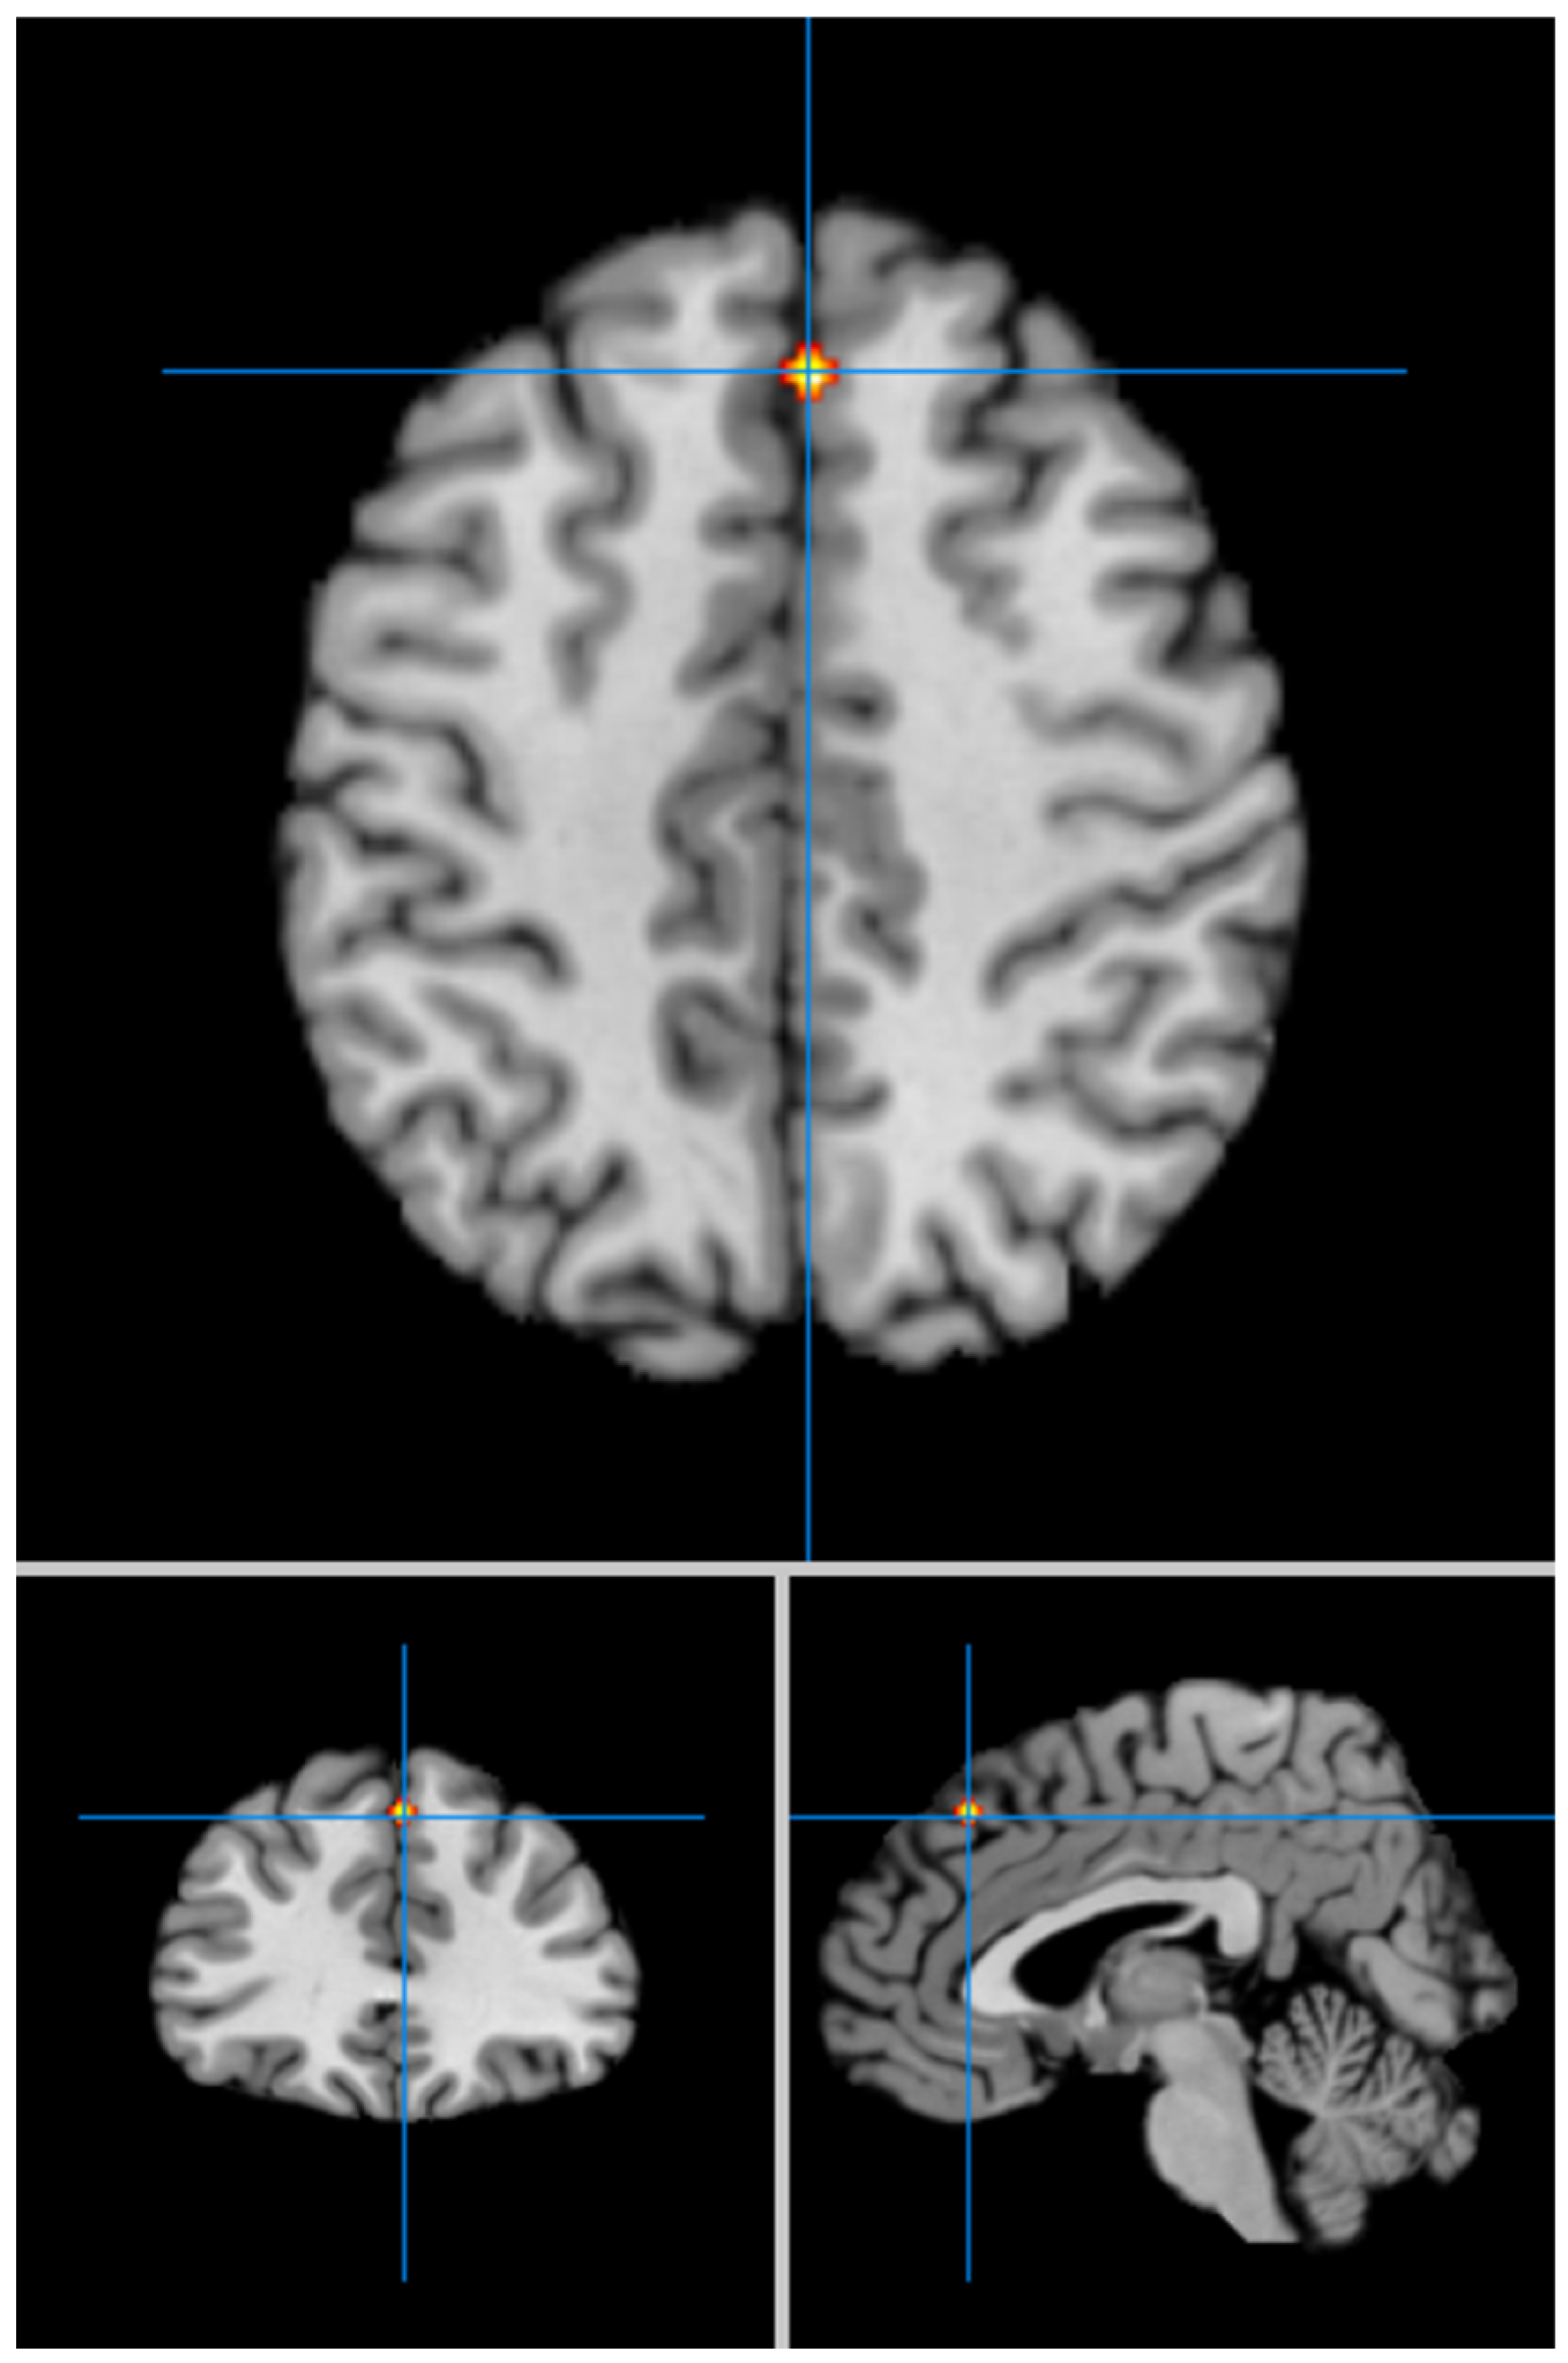

| Contrast: LLD < HCs | |||||||

| Cluster # | x | y | z | ALE | P | Z | Label (Nearest Gray Matter within 5 mm) |

| 1 | 4 | 32 | 44 | 0.017 | 2.175 × 10−6 | 45.939.293 | Right Medial Frontal Gyrus, BA 8 ** |

| 2 | 14 | 46 | 12 | 0.015 | 9.261 × 10−6 | 4.282.004 | Right Medial Frontal Gyrus, BA 9 * |

| 3 | −20 | −10 | 48 | 0.013 | 2.789 × 10−5 | 4.029.988 | Left Cingulate Gyrus, BA 24 * |

| 4 | −20 | 6 | 14 | 0.012 | 8.703 × 10−5 | 37.539.575 | Left Putamen * |

| 5 | −18 | 4 | 16 | 0.012 | 8.883 × 10−5 | 3.748.818 | Left Caudate Body * |